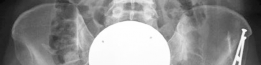

Radiographic assessment must be exhaustive. A standardized anteroposterior (AP) radiograph of the pelvis, centered over the symphysis pubis with neutral pelvic tilt and rotation, is mandatory. On this view, the LCEA, Tönnis roof inclination angle, and extrusion index are calculated. For instance, an LCEA of 18° and a roof inclination of 20° confirm severe lateral and superior uncoverage. A false profile view of the Lequesne and de Sèze is critical for assessing anterior coverage (anterior center-edge angle) and anterior joint space. Dunn 45° and 90° views, or a cross-table lateral, are utilized to evaluate the femoral head-neck junction for CAM morphology.

Advanced imaging is non-negotiable in the revision setting. A high-resolution MRI or MR arthrogram of the hip is required to assess the articular cartilage, the integrity of the ligamentum teres, and the state of the remaining labrum or capsular scar tissue. Anterolateral loss of joint cartilage is a frequent finding in dysplastic hips post-labral resection. Furthermore, a CT scan or MRI utilizing torsional sequences from the hip through the knee is essential to quantify femoral version. A measured femoral anteversion of 36° dictates that a derotational femoral osteotomy (DFO) must be incorporated into the surgical plan to restore normal biomechanics and prevent recurrent anterior subluxation post-operatively.